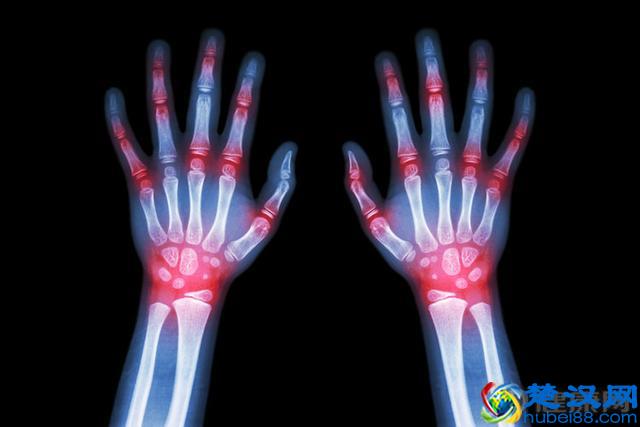

痛风是体内嘌呤代谢紊乱伴有血尿增高引起组织损伤的异质性疾病;它是在高尿酸血症的基础上伴有反应性关节炎或痛风石等病变。

痛风多为40岁以上的男性,有肥胖、嗜酒等诱发因素,部分患者有家族遗传史,典型症状是关节炎,大多数为下肢趾关节剧痛,半夜发作,白天得以缓解。以下标准中符合两项,即可诊断为痛风。

血尿酸男性>70mg/L,女性>60mg/L

有痛风石

关节液内找到尿酸钠结晶或组织内有尿酸钠沉淀

有两次以上发作

下肢远端关节突然发作,夜剧昼缓

用秋水仙碱治疗后,48小时内可缓解